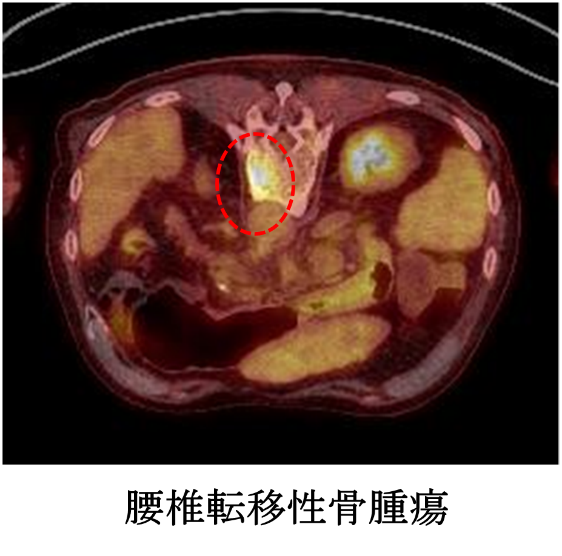

軟部腫瘍のMRI | 青木 隆敏, 青木 隆敏 |本 | 通販 | Amazon